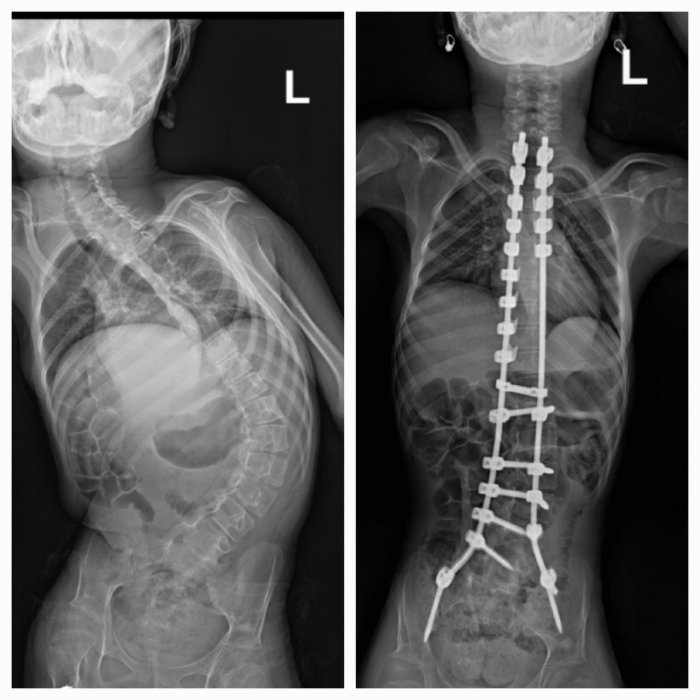

Among the recent cases conducted by the Hospital was a 14-year-old patient who was suffering from cerebral palsy, severe scoliosis and inclination of the spine. The spine was fully straightened and adjusted quickly and efficiently, as the surgery took only 4 hours. After that, the patient recovered and became able to function independently, and she left the hospital 4 days after the surgery.

Regarding the stages of scoliosis diagnosis, Prof. Abdulmonem Al-Siddiky explained that the method of diagnosis in different cases requires an initial clinical examination on the back and of the height of the shoulders, and the specialist doctor may, in some cases and prior to the necessary treatment, request an X-ray to diagnose the disease and measure the angle of deviation, as well as CT scans and resonance imaging to ensure the integrity of the cord and spine.

Prof. Abdulmonem Al-Siddiky explained that this disease sometimes leads to movement difficulties for the patient, as well as difficulty in understanding and communicating with others, and is often accompanied by deviations in the spine, as a result of weakness in the bones and muscles, and this in turn represents a challenge in the installation of medical tools and the use of surgical tools, and in fixing the screws as well, along with the challenge of chiropractic, indicating that the deviations often have a rigid aspect due to the stiffness and inflexibility of the spine, and this leads to an inclination in the back and an imbalance in the shoulders, as well as an imbalance in the patient’s pelvis.